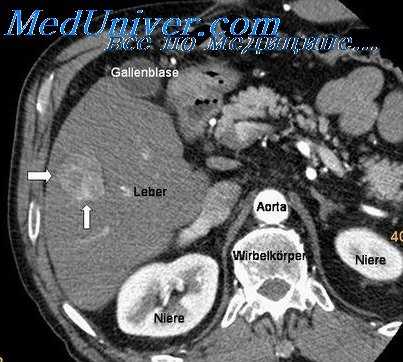

Хотя бы частично решить эту проблему позволяют продуманные планы первичного и последующих обследований, составленные с учетом возможности развития первично множественных опухолей. Так, при локализации солитарного новообразования в зоне молочной железы специалисты уделяют пристальное внимание состоянию второй молочной железы и внутренних женских половых органов, при расположении неоплазии в области желудка – состоянию толстого кишечника, кожи, яичников, матки и молочных желез и т. д. План обследования в каждом конкретном случае составляется индивидуально. Решающую роль при постановке диагноза обычно играют радиологические методики (рентгенография, КТ), УЗИ, МРТ и гистологические исследования.